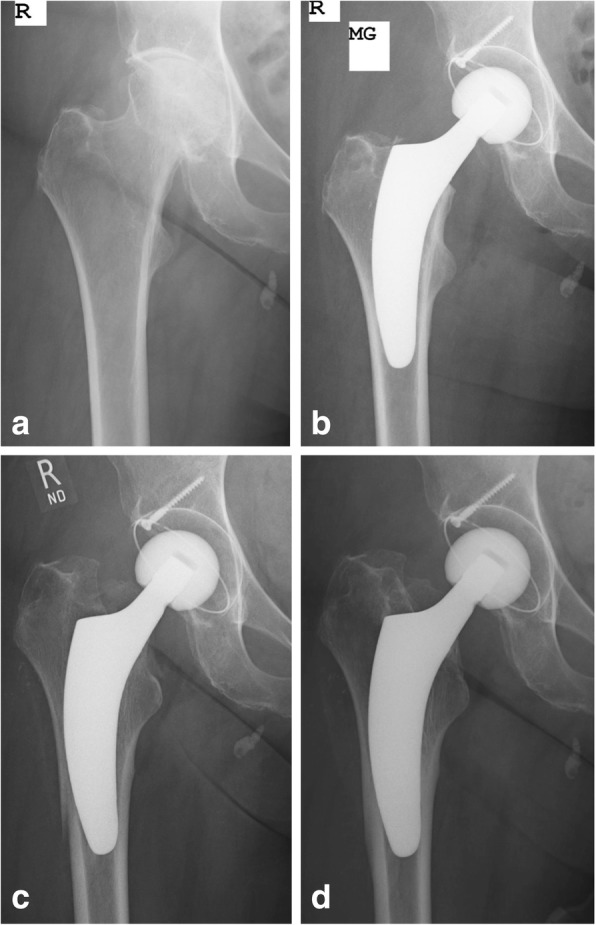

Postoperative periprosthetic femoral fractures during follow-up were observed in 0.4% in the young group and 3.6% in the elderly group respectively, the difference being statistically significant (p = 0.02). Three of these periprosthetic fractures led to stem revision and the other 3 were successfully treated conservatively with no weight bearing using crutches (Figs. 3 and 4). Whereas in Dorr type A femurs no postoperative periprosthetic fracture was observed at all, in type B femurs a total of 4 fractures occurred and in type C femurs a total of 2 fractures occurred respectively. Thus, the incidence of postoperative periprosthetic fractures in Dorr type B and Dorr type C femurs was 2.1 and 22.2%, respectively (p = 0.0001) (Table 5).

Fig. 3.

Example of postoperative periprosthetic fracture Vancouver type B3 due to accidental fall of an elderly female patient followed by stem revision (a: preoperative; b: postoperative; c: periprosthetic fracture; d: after stem revision)

Fig. 4.

Example of postoperative periprosthetic fracture Vancouver type B in the course of severe subsidence in an elderly female patient treated conservatively (a: preoperative; b: postoperative; c: periprosthetic fracture with severe subsidence; d: follow-up after 24 months)